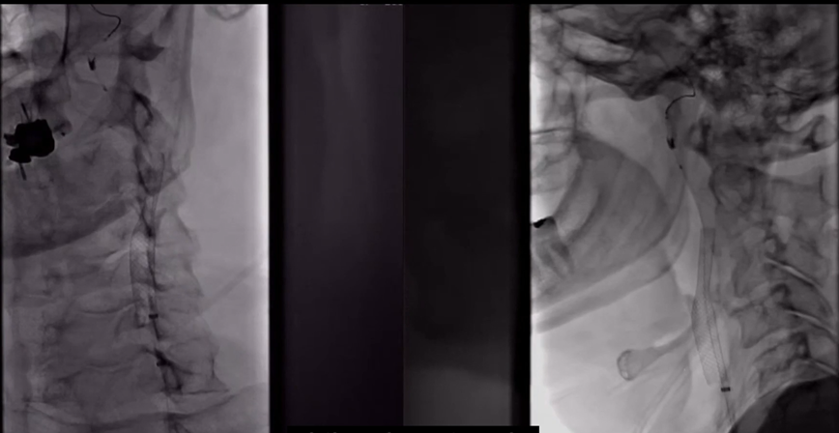

患者男性,66岁,以“言语不清伴左侧肢体无力1天”入院,既往高血压病史、吸烟史。查体:构音障碍,伸舌左偏,左侧上下肢体肌力4级,左侧上下肢针刺觉减退,左侧Babinski征阳性。NIHSS评分:5分(言语1分,面瘫1分,左上肢1分,左下肢1分,感觉1分)。术前头DWI:右侧额颞顶枕叶急性分水岭脑梗死;CTA:双侧颈内动脉起始部重度狭窄;CTP:右侧大脑半球CBF↓,MTT、TTP↑。

DSA:双侧颈内动脉起始部重度狭窄;前交通及双侧后交通未开放。

8F Fluxcap®球囊导引导管在5FMPA多功能125cm导管同轴辅助下送至右侧颈总动脉,微导丝送至C4段,沿微导丝送入6mm保护伞至C2段平直段,手推造影显示保护伞打开良好。

沿保护伞导丝送入4.0mm×30mm球囊,充盈球囊导引导管的球囊阻断血流,于狭窄段定位后命名压扩张球囊,泄球囊时在球囊导引导管的体外端予以负压回抽血液,取出一2mm血栓。经Fluxcap®球囊导引导管输送7.0-10.0mm×40mm自膨支架(Protégé RX)至狭窄段确认位置后释放。应用125cm多功能导管回收保护伞,多功能导管体外端予以负压回抽血液,保护伞内有血栓。

造影可见残余狭窄10%左右,颅内各分支血管通畅。